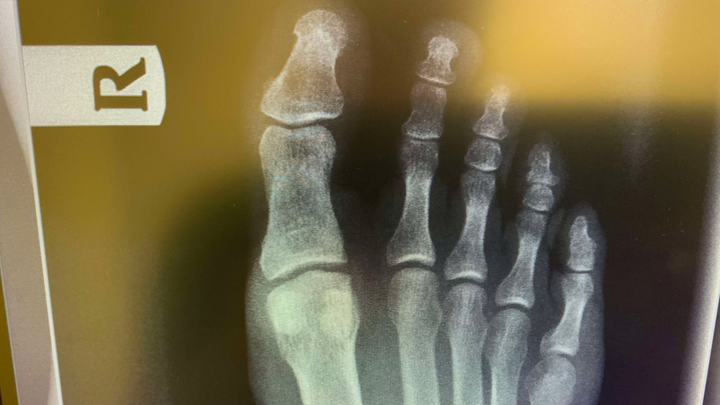

I'm an author and journalist with an amazing family and a small desert ranch in Southern California. I love our little hobby farm, but unfortunately it was one of our 250-lb goats that stepped on me almost nine months ago and broke a small bone in my right foot. My surgeon informed me that it hasn't healed, and that it won't heal, so he needs to remove the bone itself to keep the pain from lasting my entire life (fortunately, as he says, this bone is the tonsils of the toes, in that it is removable without ruining my ability to walk long term). I actually have health insurance, but the surgery is $18,000, and my plan only covers $10,000 of that. I'm expected to pay $8,000 up front at the time of surgery, which is in 10 days, and there are also special shoes and inserts, etc., I will need for recovery. In total, my share of the costs will be around $12,000. With the cost of maintaining about 100 total rescue animals on our ranch, I know I can't do that alone. I'm really hoping some of you out there are willing to chip in and make this a little easier. I sincerely appreciate all of you who read this, and those who contribute have my undying gratitude. Thank you all.